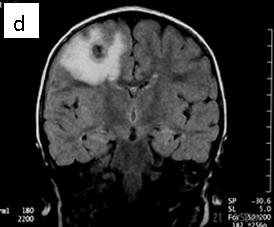

Figure 1: Neurocysticercosis in an 18-month child. a. Sagittal T1 without gadolinium; b. Axial T1 with gadolinium; c. Axial T2; d. Coronal FLAIR

Radiologic diagnosis: Neurocysticercosis.

| MRI | Live forms have a characteristic appearance: fluid-filled lesions containing an inverted scoleces, surrounded by thin low-signal capsule. They do not stimulate inflammation and do not enhance; dying forms do. In the less common racemose type, the cysts may be hard to see because they have similar imaging features as the CSF. |

For cysts that cause symptoms outside the CNS, surgical resection achieves cure. The treatment of symptomatic neurocysticercosis, which carries a 50% mortality rate, is more problematic. Two drugs, albendazole and praziquantel control symptoms and cause regression in the size and number of cysts in patients with viable (non-enhancing) cysts in their brain parenchyma. However, they provide limited improvement in patients with arachnoiditis and none in patients with intraventricular cysts. These latter patients should be treated with surgery or palliated with ventricular shunting, anticonvulsants, and anti-inflammatory drugs. According to our case’s physician, he did not receive anti-parasitic medication because the imaging features suggested that the parasites were dying (vasogenic edema and ring enhancement) (6).